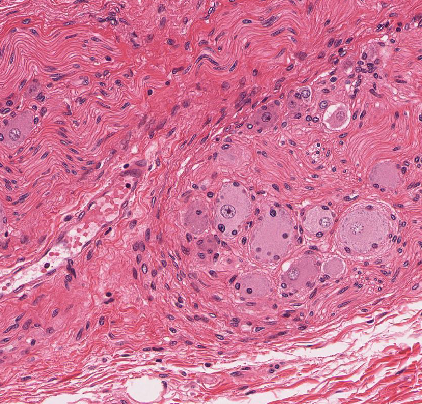

Dorsal Root Ganglia

Contain the cell bodies of sensory neurons.

The neuron cell bodies belong to large, pseudounipolar sensory neurons that have a single “T-shaped” process; these are the afferent fibers carrying sensory information from the periphery (sensory receptors in the skin, joints and muscles that respond to touch, temperature, pain, stretch) to the dorsal horn, where they synapse on neurons in the spinal cord.

NOTE: these sensory neurons are an exception to the typical neuron, in that they do not have separate dendrites and an axonal process, but rather one branched process that serves both functions.

sensory ganglia

pseudounipolar neurons, high neuron density, large # of satellite cells, and NO synapses.